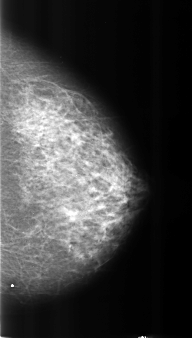

B_3222_1.LEFT_CC

LEFT_CC LINES 4384 PIXELS_PER_LINE 2488 BITS_PER_PIXEL 12 RESOLUTION 50 NON_OVERLAY